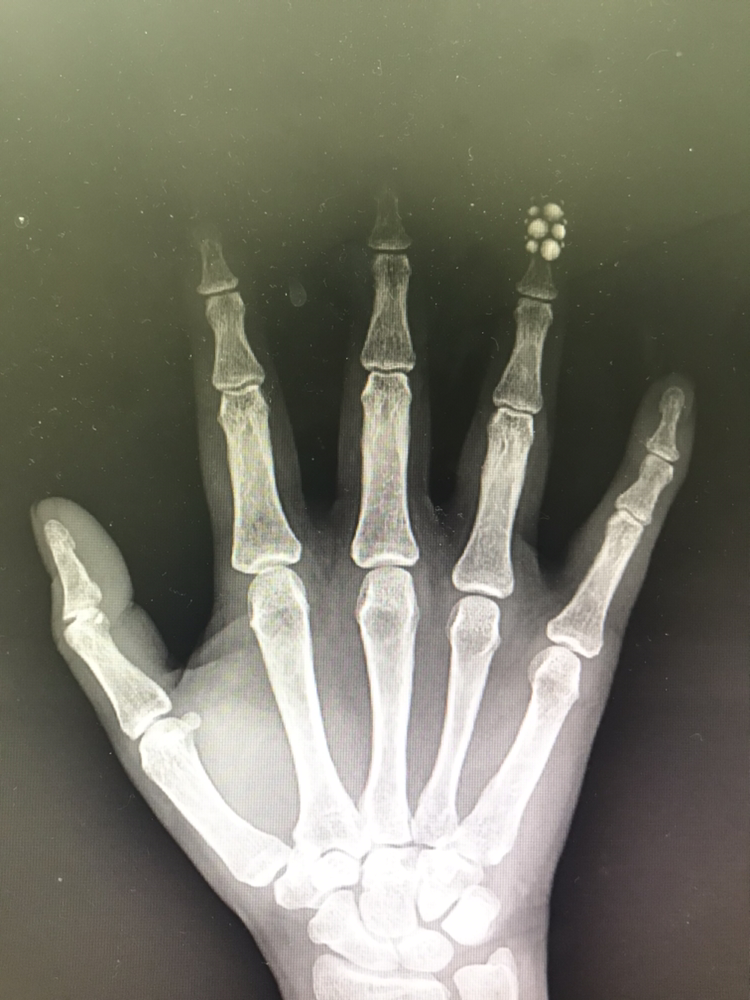

설거지 하시다 철사에 손바닥 찔려서

피 철철 흘리시던 분인데,

다행히 큰 탈은 없었습니다.

약지의 네일아트가 시선을 화들짝 강탈하네요.